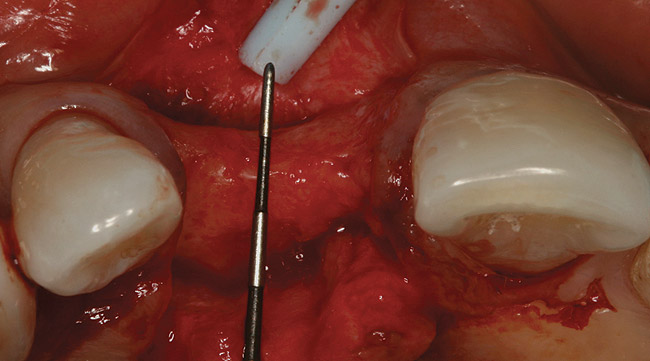

A long diamond bur was used to make a cut, which was 6-mm to 8-mm deep in the center of the alveolar ridge (Figure 3). The cut was made at least 1 mm away from the adjacent teeth in order to prevent any damage to them. A 4-mm wide bone-spreading chisel was used to mobilize and displace the buccal plate facially (Figure 4) so that a small, tapered osteotome for expansion could be used for implant site preparations. A 2-mm round bur was used to mark the implant location, and a 2-mm twist drill was used to guide the expansion with osteotomes.

Figure 3  Initial crestal corticotomy/depth cut.

Figure 3

Figure 4  Initial expansion with ridge-splitting chisel.

Figure 4